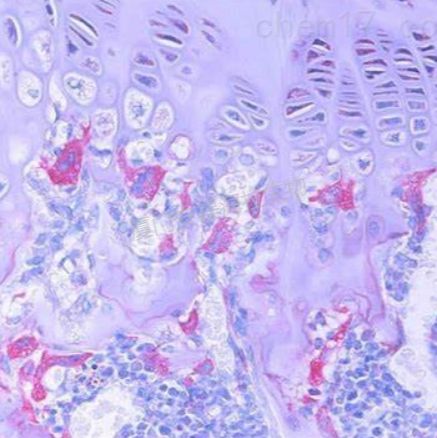

番红固绿染色(动物)

服务介绍: 番红-固绿染色(软骨)在涉及关节软骨及软骨下骨的形态学研究中,常需联合使用多种染料以显示其组织学结构。其中,起源于上世纪60年代的番红O(safranin O)-固绿(fast green)染色因可以直观反映关节软骨、软骨下骨和骨组织的结构而备受青睐。软骨呈红色,成骨